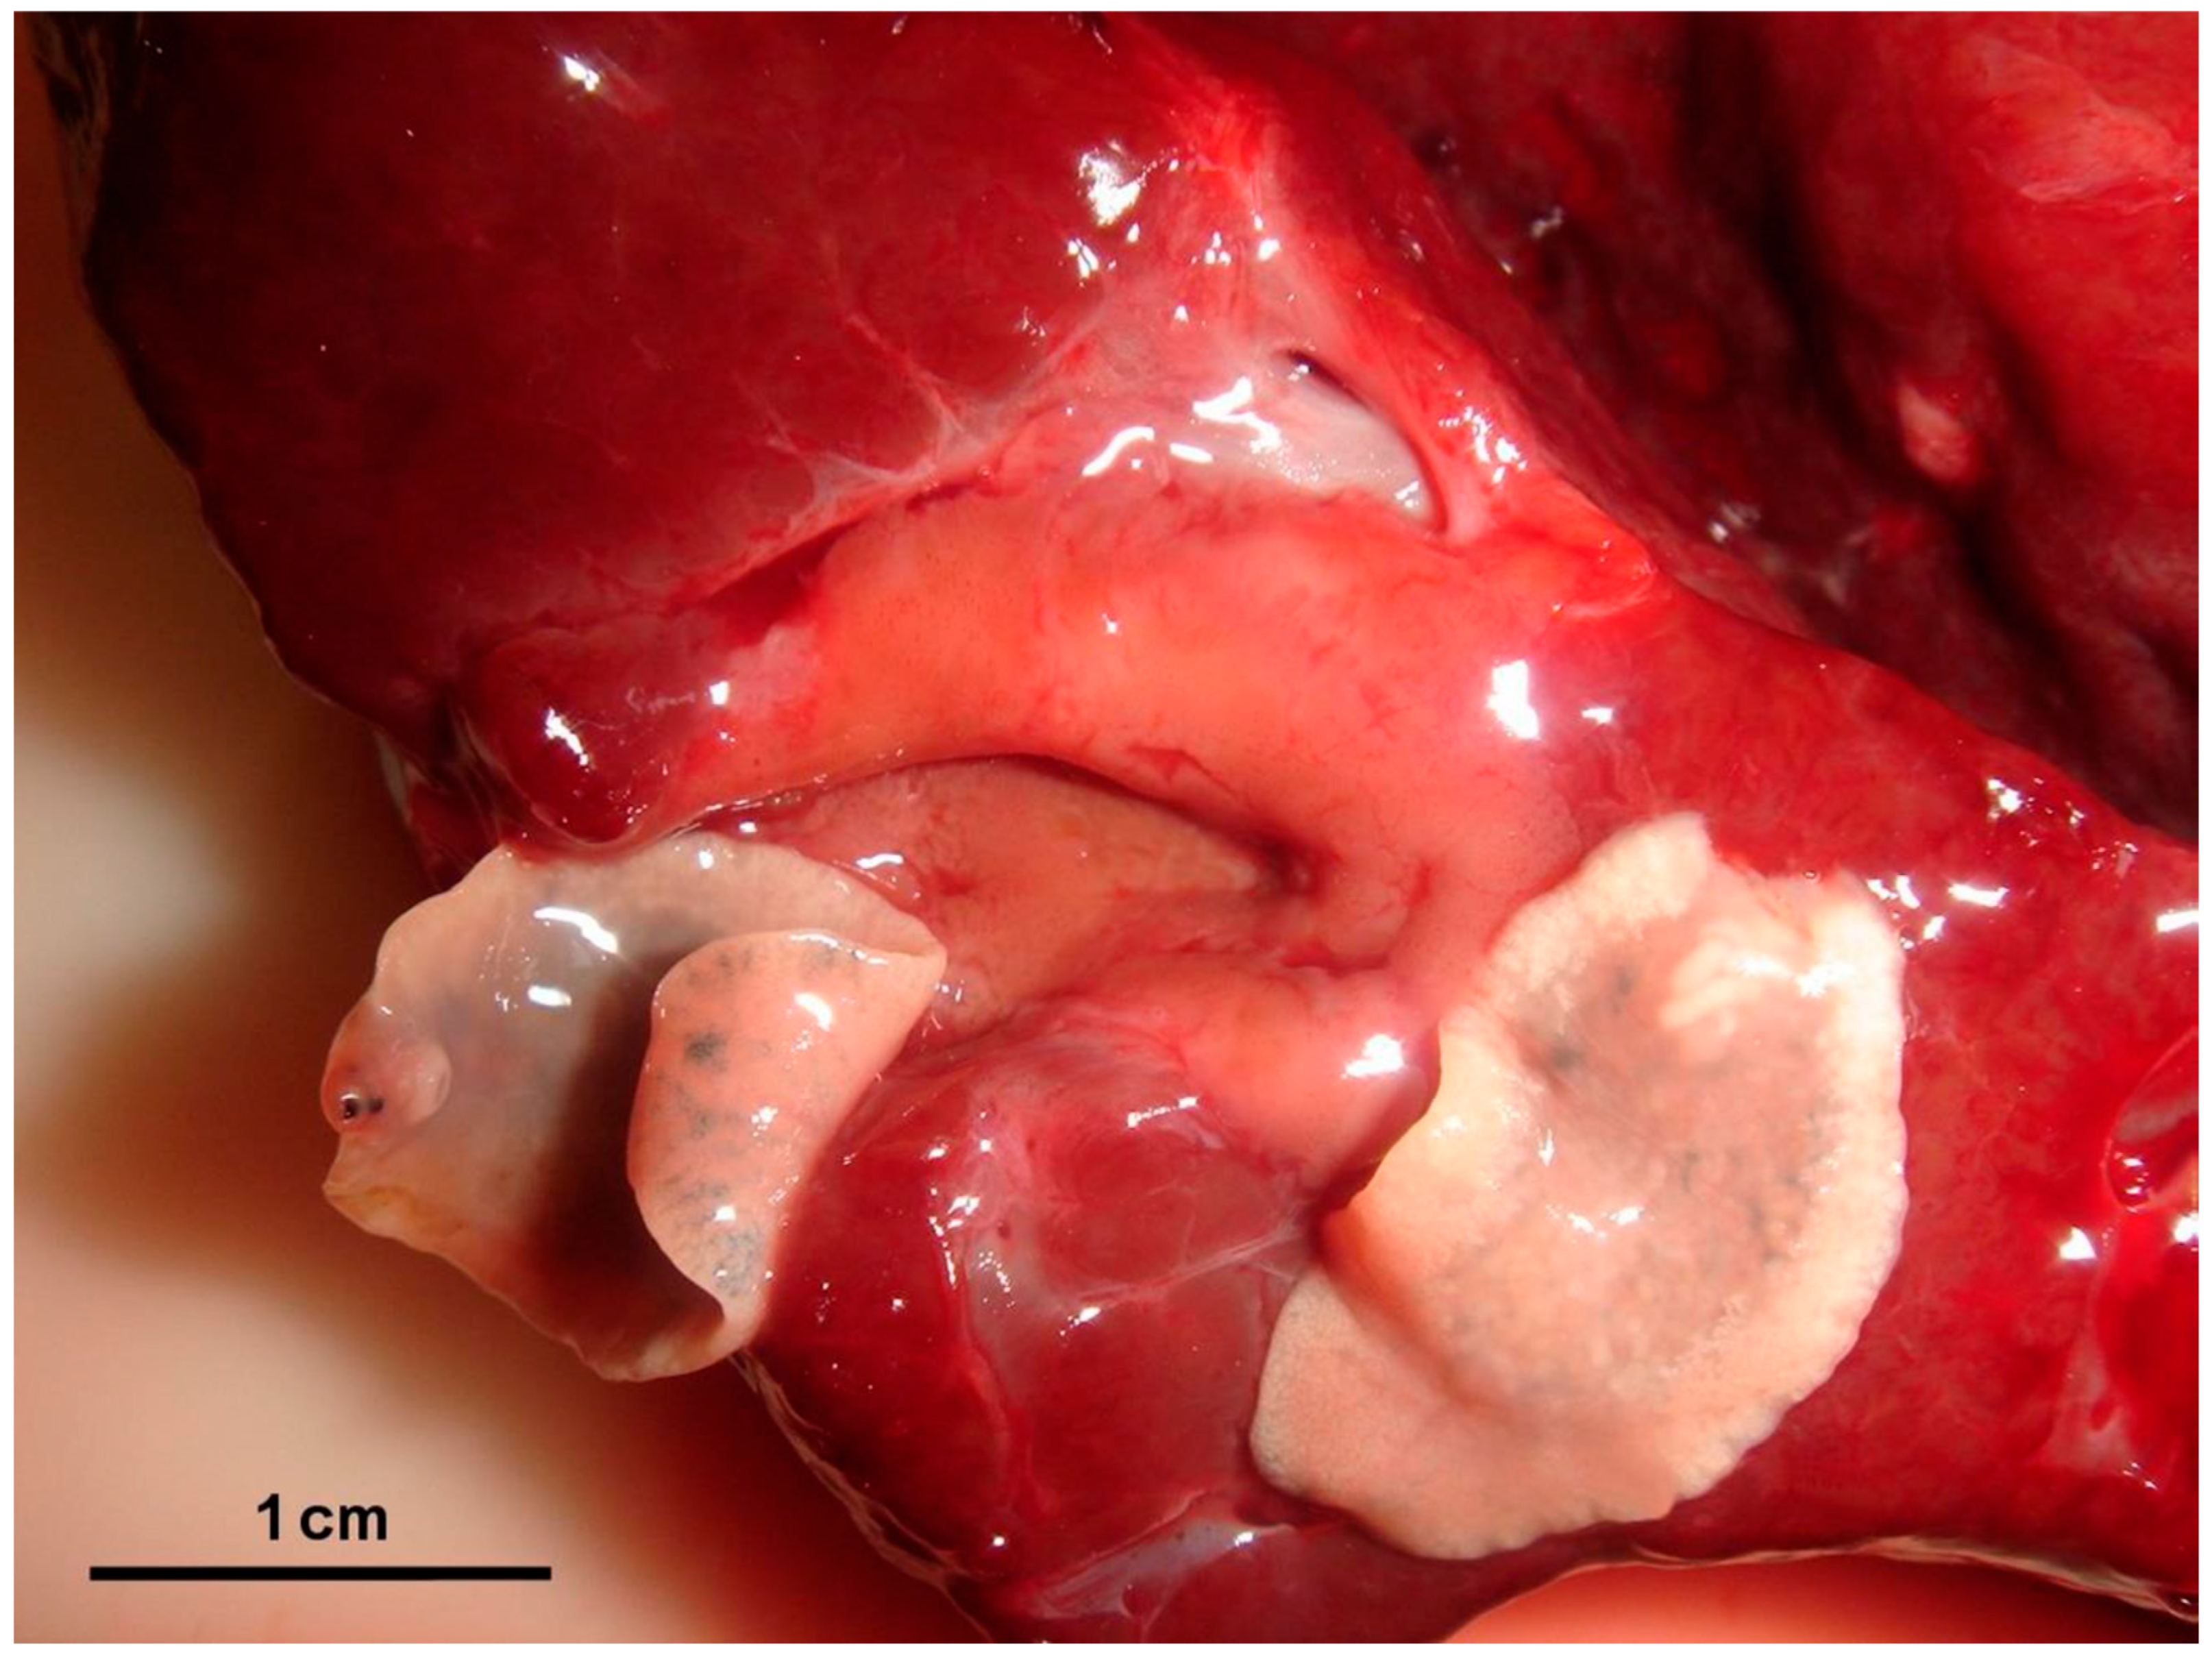

3.1. Necropsy